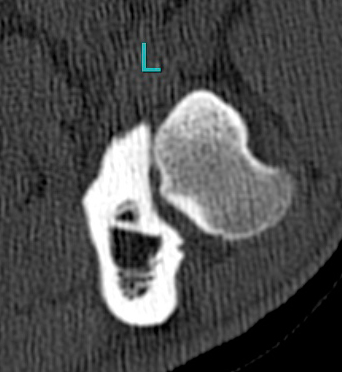

- Left leg once again

- Well this is clearly a view on a joint. Also left.